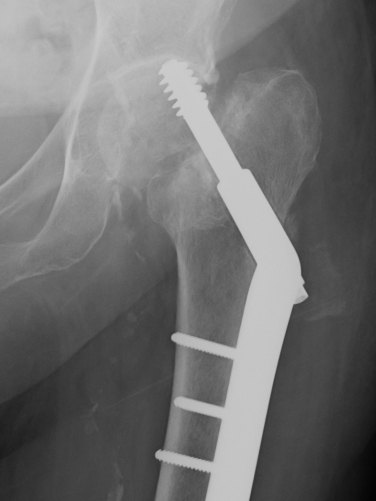

DHS versus nail

Depends on stability

Requires intact lateral wall for DHS (or GT plate)

- post-operative fracture of lateral wall turns stable intertroch into unstable

- Norwegian hip registry review of 17341 patients

- DHS vs nail for unstable intertrochs (A1/2/3)

- Nails have lower re-operation, and lower mortality rate

- meta-analysis of 22 studies and 3000 patients including all types of extracapsular proximal femur fractures

- DHS v cephalomedullary nail

- no difference in mortality / reoperation / failure fixation / complications

- IMN had shorter operative times and reduced blood loss

- Did no delineate between fracture patterns

Malunion

Excessive lateral sliding / shaft medialisation

Cause

- collapse with insufficent lateral buttress

- reverse obliquity fracture